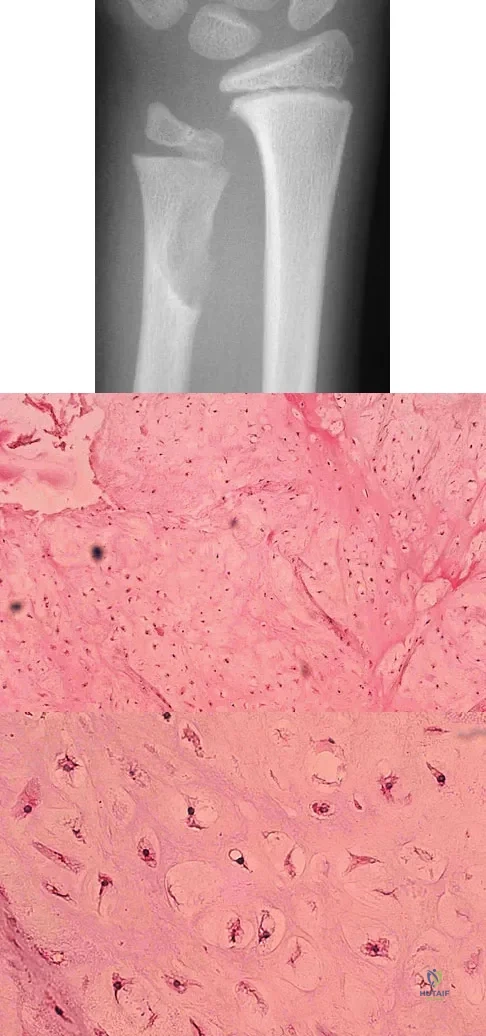

A 20-year-old woman has had wrist pain for the past 5 months. A radiograph, MRI scans, and biopsy specimen are shown in Figures 46a through 46d. The patient is then treated with intralesional surgery. The patient should be counseled that her risk of developing lung metastasis is approximately what percent?

A 10-year-old boy has had wrist pain for the past 3 months. He denies any history of trauma. He reports mild tenderness associated with a palpable mass. A radiograph and biopsy specimens are shown in Figures 52a through 52c. What is the most likely diagnosis?

A 29-year-old woman reports shoulder pain after sustaining a minor fall 6 weeks ago. She has a history of celiac sprue. Radiographs of the forearm and shoulder are shown in Figures 53a and 53b. Which of the following serum abnormalities would be expected?